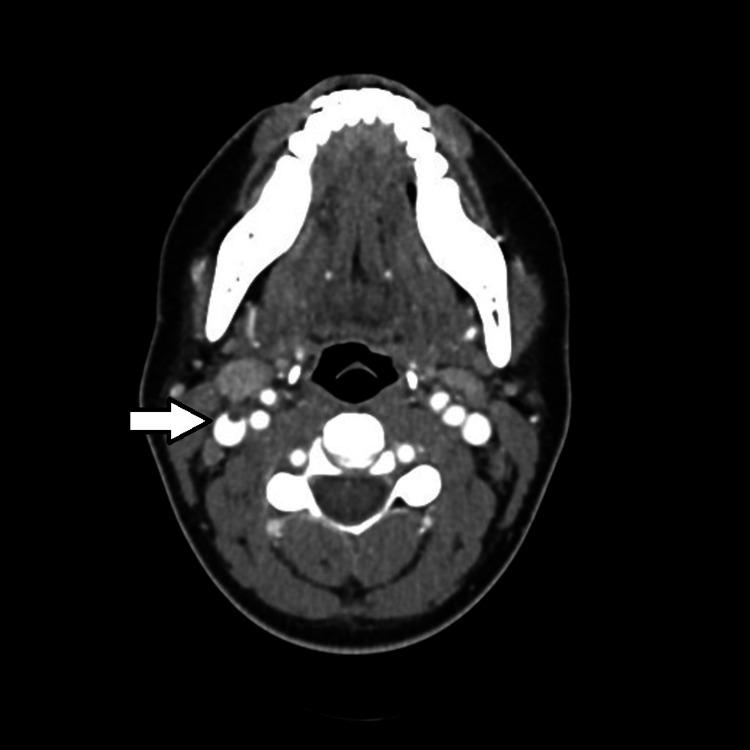

勒米尔综合征是一种口咽感染发展为败血症和颈内静脉血栓性静脉炎的病症。尽管自从广泛使用抗生素治疗链球菌性咽炎以来,该综合征的发病率已大幅下降,但对于出现咽炎持续时间延长、颈部侧方疼痛和败血症症状三联征的其他方面健康的年轻患者,仍应怀疑此病。在本报告中,我们探讨了一例并发高凝状态且初始抗生素治疗无效的勒米尔综合征的独特病例。